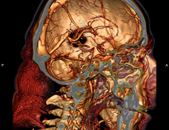

CT Kopfaufnahme 2005